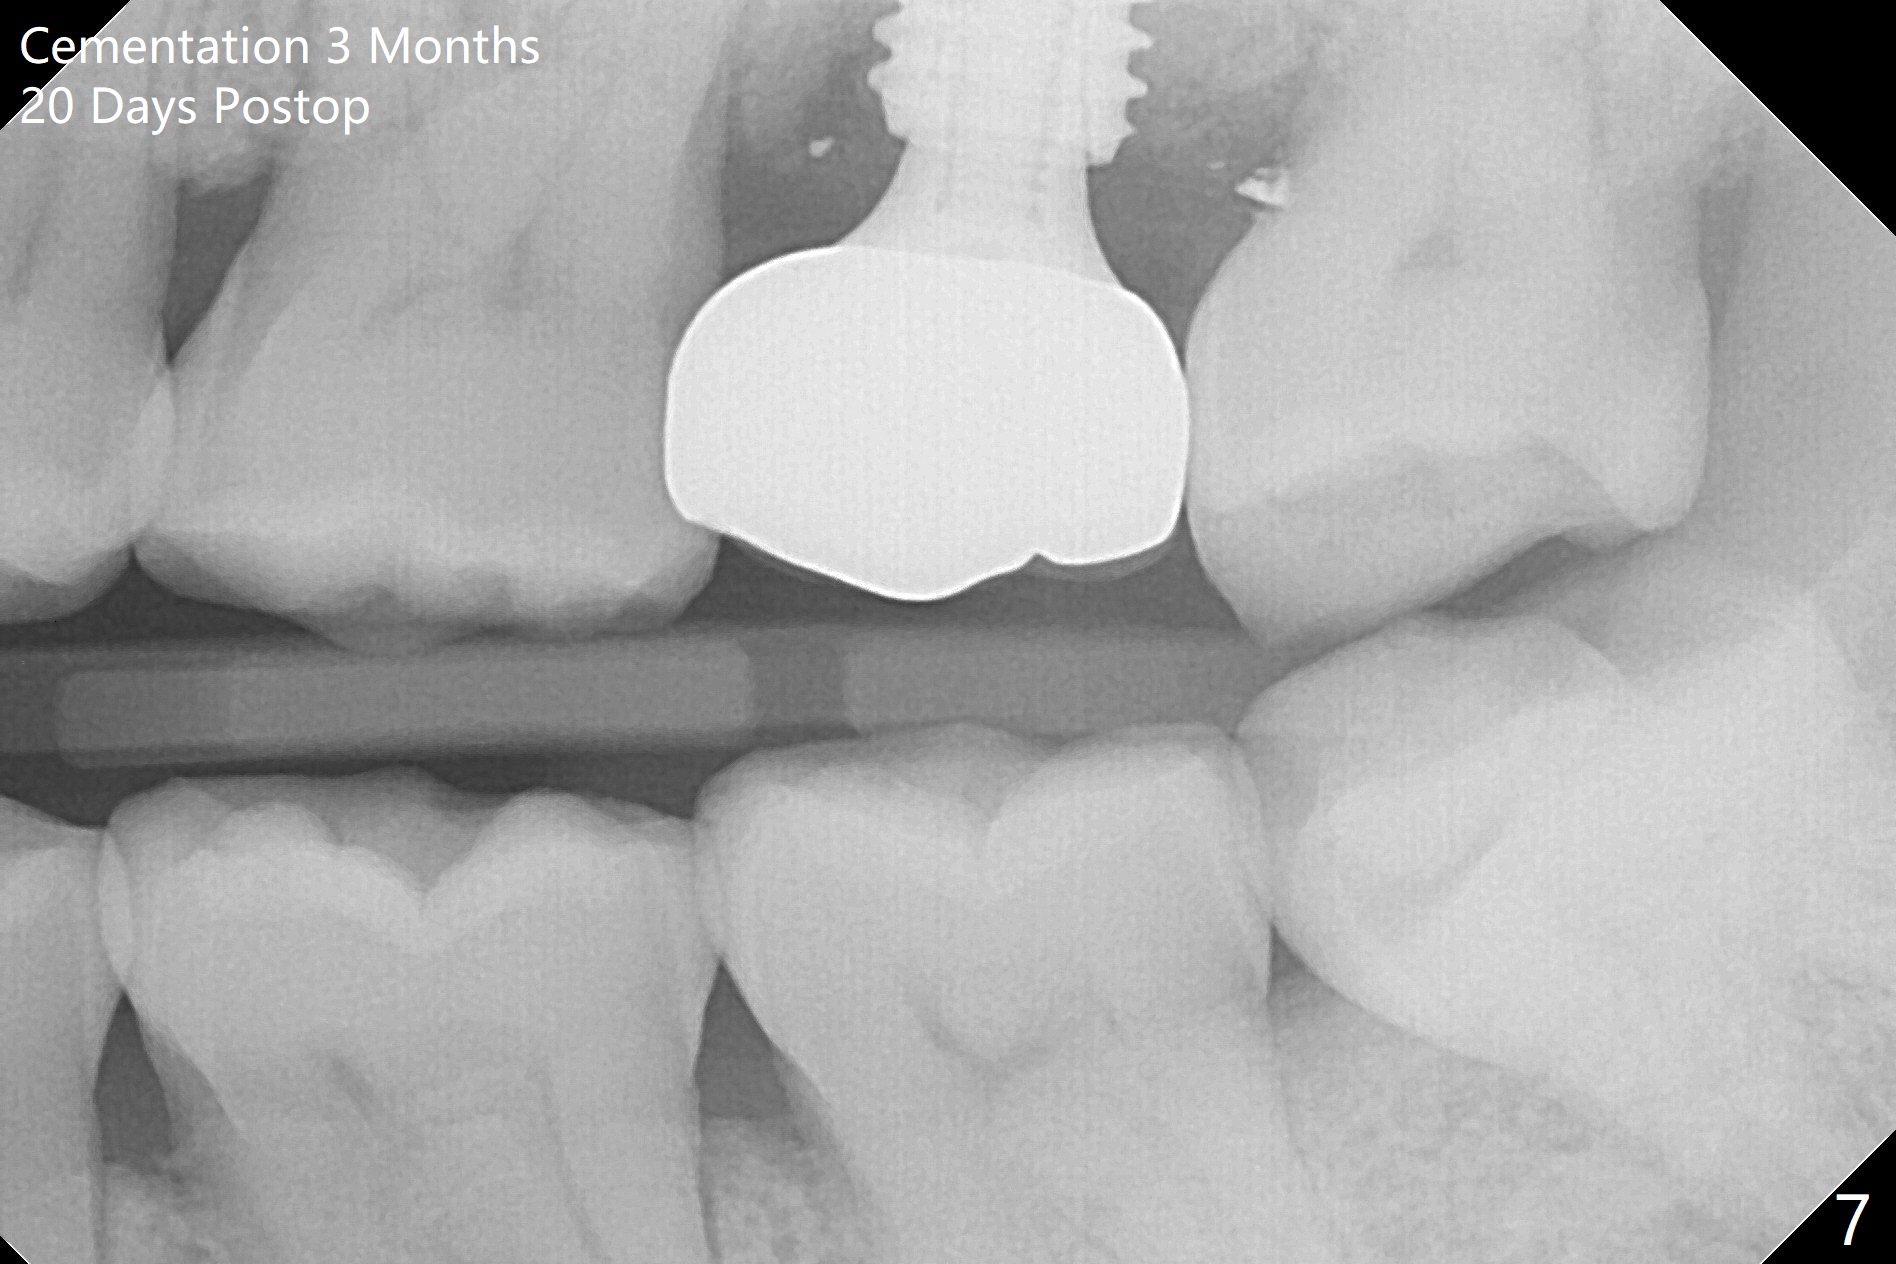

When the patient returns for the tooth #15 extraction and implant, the mesiobuccal residual root has been expelled, while the distobuccal and palatal roots seem to have extruded (Fig.1). The mesial portion of the gingiva (G) is intact and thick. The trajectory of the initial osteotomy is to be changed as shown by red line in Fig.2. The 3.8 mm drill appears to be distal (Fig.3). With mesial bone removal with Lindamann bur, the position of the final implant (5x13 mm) is within normal limit (Fig.4 (50 Ncm)). Because of the thick mesial gingiva (Fig.4 G) and placement of the 5.5x4(2) mm abutment, insertion of mixture of autogenous and Vanilla Graft (*) into the mesial aspect of the implant is difficult (Fig.4 >). Further pushing of the bone graft from the buccal and palatal socket gaps results in more ideal packing (Fig.5 >). If the bone graft were placed first, packing would have been easier. An immediate provisional is fabricated to prevent further mesial shifting of the 3rd molar (Fig.1 arrow). The implant remains stable, while the provisional and abutment are loose 3 months 1 week postop (Fig.6). Impression is taken after abutment cleaning and retightening. Because of the long implant (13 mm), a permanent crown can be cemented early (3 months 20 days postop, Fig.7).